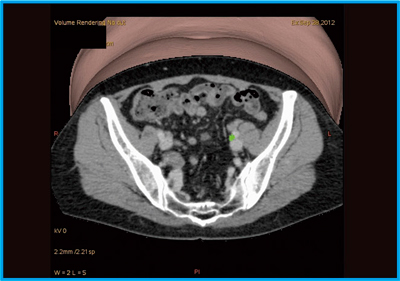

●症例9:子宮体がん術前のLymphoscintigraphy

症例9は,子宮内膜から腫瘍周囲に薬剤を投与後,時間を空けてLymphoscintigraphyを撮像し,そのまま手術を行った。Lymphoscintigraphyで,センチネルリンパ節と思われるhot nodeが確認できた。しかし,婦人科医の要望はセンチネルリンパ節と血管との位置関係の把握であったため,診断に用いた造影CTデータで血管の3D VR画像を作成し,吸収補正用CTデータを介してSPECTとフュージョンした(図13)。緑色に表示したセンチネルリンパ節が外腸骨動脈に存在していることが認められるが,さらに位置関係を明瞭にするため,造影CTデータを3Dで切り出して重ねることで,ピンポイントで目的となる部位を示すことができた(図14)。

![]() 図13 症例9:子宮体がん術前のSPECT/CT-造影CTフュージョン画像 |

![]() 図14 症例9:SPECT/CT-造影CTフュージョン3D横断像 |